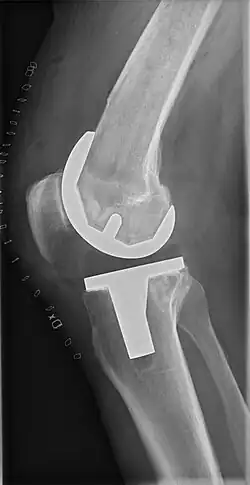

El reemplazo de rodilla se evalúa de forma rutinaria mediante rayos X, incluidas las siguientes medidas:

-

CRT: Ángulo cadera-rodilla-tobillo, que idealmente está entre 3° en varum y 3° en valgum desde un ángulo recto.[54] -

- CFF: ángulo del componente femoral frontal. Por lo general, se considera óptimo cuando se encuentra entre 2 y 7° en valgo.[55]

- CTF: ángulo del componente tibial frontal, que se considera óptimo cuando se encuentra en ángulo recto. En general, se ha encontrado que una posición en varo de más de 3 ° aumenta la tasa de falla de la prótesis.[55] -

- La entalladura femoral anterior (el componente femoral que causa una reducción del grosor del fémur distal en la parte anterior) parece aumentar el riesgo de fracturas cuando excede aproximadamente 3 mm.[56]

- CTL: ángulo del componente tibial lateral (o sagital), que está idealmente posicionado de modo que la tibia esté flexionada de 0 a 7° en comparación con un ángulo recto con la placa tibial.[55]